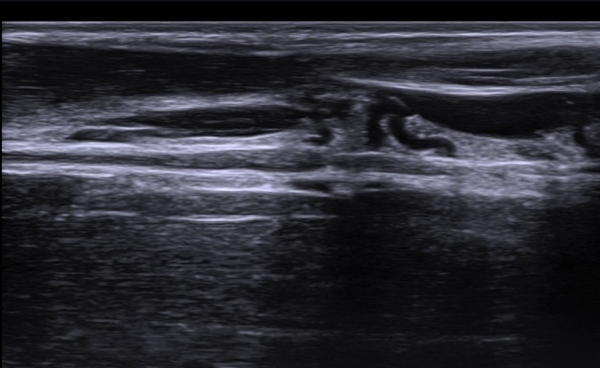

Å½ÃËÀÚ¸¦ Á¶±Ý ¸»´ÜÀ¸·Î À̵¿ÇÏ´Ï ±ÙÀ°ÇǺνŰæÀÇ À§ÃàÀÌ °üÂûµÇ°í(»çÁø 2) ŽÃËÀÚ¸¦ Á¶±Ý ´õ

¸»´ÜÀ¸·Î À̵¿ÇÏ´Ï ±ÙÀ°ÇǺνŰæÀÌ Á¤»êÀûÀ¸·Î °üÂûµÈ´Ù(»çÁø 3).